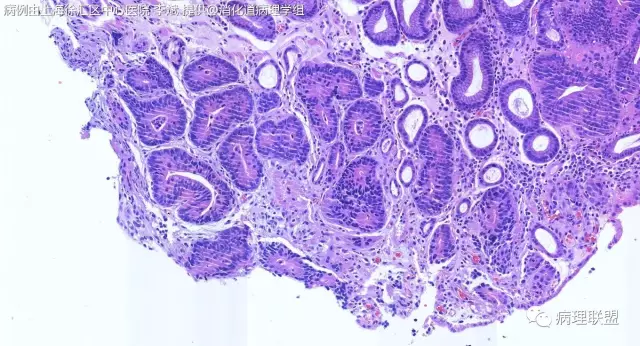

F-56 胃窦粘膜活检(低级别 vs 高级别)

女,56岁,胃窦粘膜活检(病例由上海徐汇区中心医院 李斌 提供,致谢!)

考虑:低级别上皮内病变(轻度异型增生)。

@李斌,高级别,腺体结构乱复杂,核异型性大,极向乱